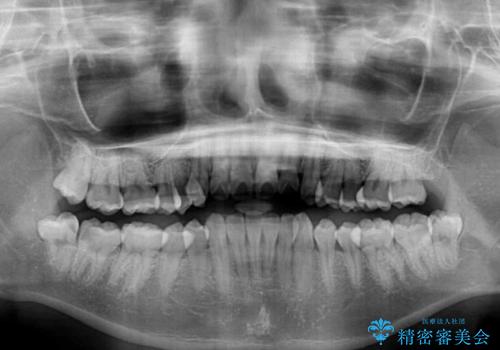

- 前歯のデコボコを気にして来院された患者様です。

叢生と捻転が随所に認められるものの、マウスピースで十分対応可能であったため、インビザラインにて矯正治療を行うこととしました。